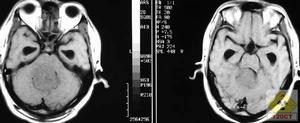

5.CT和MRI掃描 可確定腫瘤的部位和大小,絕大多數可作出定性診斷。CT掃描示邊界清晰的均勻高密度影,增強後顯著。少數呈混合密度或低密度改變。MRI見腫瘤多數呈等信號,增強後明顯強化。過去腦室內腦膜瘤主要靠腦室造影及腦血管造影診斷因此早期診斷比較困難,目前CT或MRI是該病診斷的最可靠方法。

病狀表現2.CT掃描 可以了解腫瘤的大小,位於腦室的位置,與室間孔和導水管的關係,以及是否合併腦積水平掃多可見腦室內均勻一致的稍高於腦組織密度的腫塊,無明顯鈣化增強後CT掃描表現為中等度強化,有時病灶中心可強化不均一可見腫瘤與腦室內脈絡叢相連。一般腫瘤邊界清楚,光滑,不向腦組織內侵襲。腫瘤還可引起側腦室顳角擴大和脈絡從鈣化點的移位。側腦室腦膜瘤位於三角區,有時增強CT可見腫瘤與脈絡叢相連側腦室可見擴大。

3.MRI掃描 側腦室腦膜瘤在MRI的信號與其他部位腦膜瘤基本相似。但MRI與CT相比能更清楚地顯示腫瘤輪廓和周圍水腫帶更好地顯示腫瘤與室間孔中腦導水管側腦室壁及周圍重要腦組織結構的關係,對手術有一定指導意義另外,MRI掃描能發現三腦室和四腦室內較小的腦膜瘤,但需要注意鑑別。